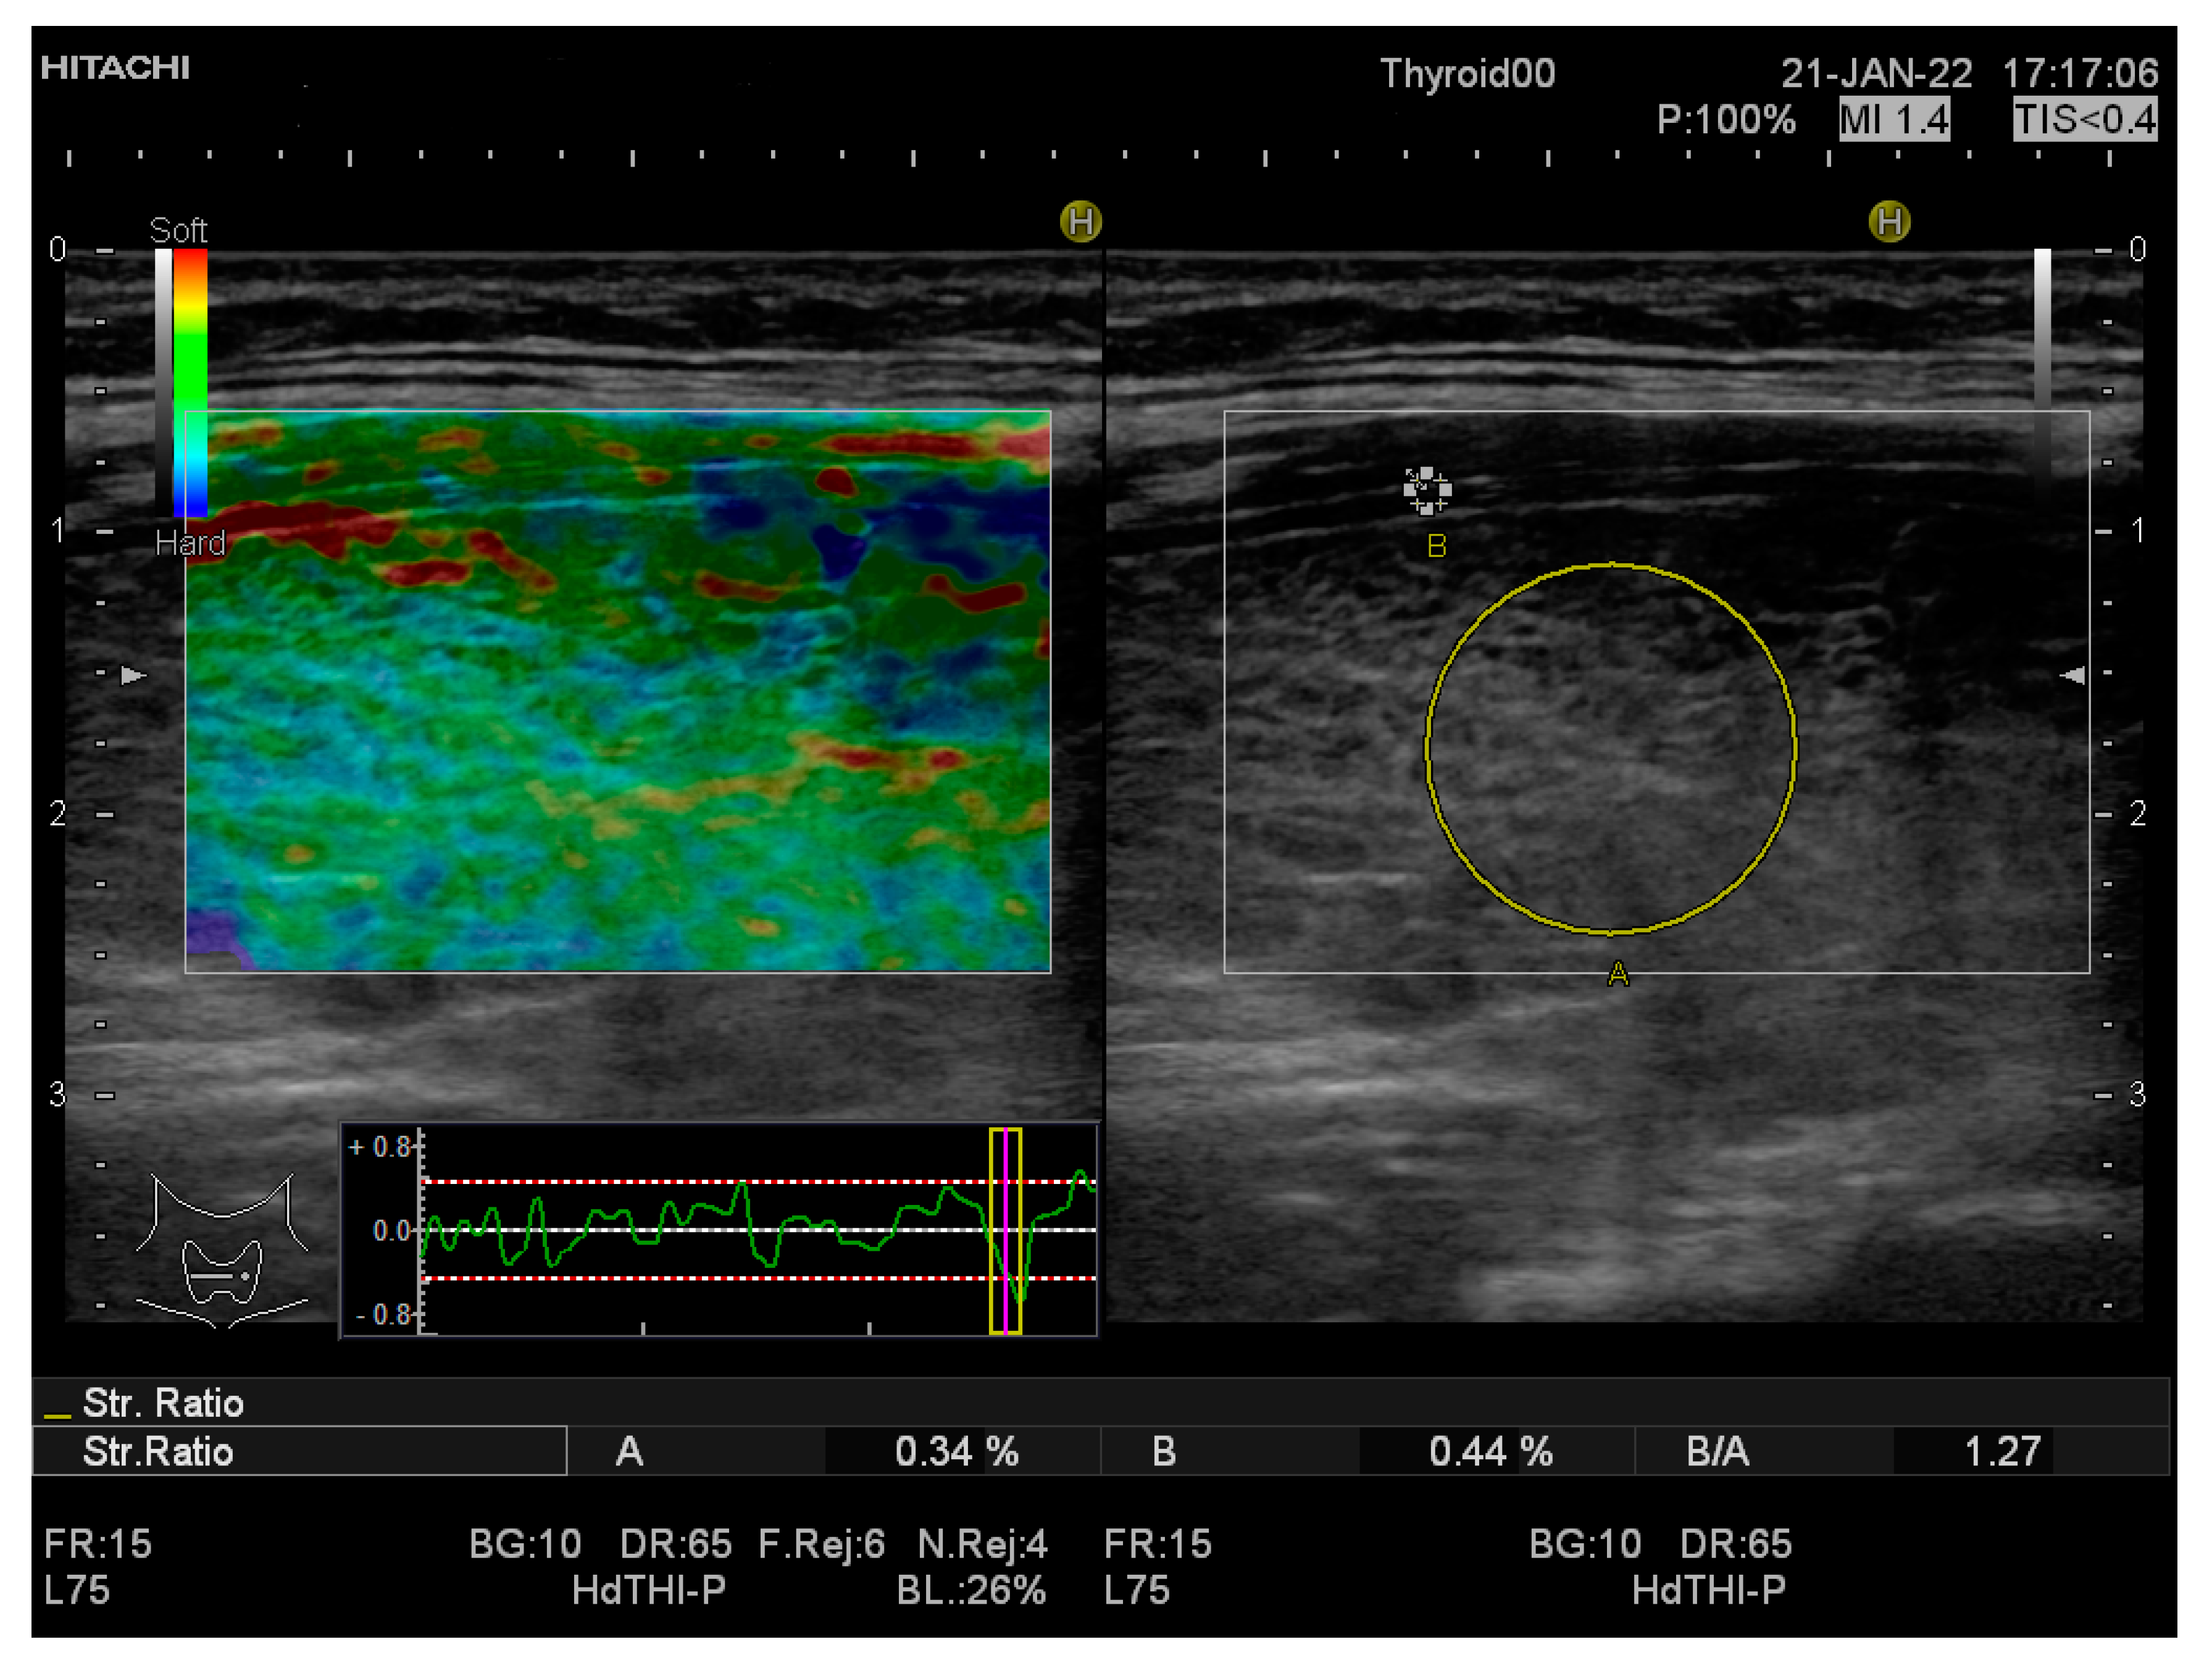

| SR mean value | 1.19 ± 0.25 | 0.68 ± 0.2 | <0.0001 |

| SR-LTL | 1.20 ± 0.31 | 0.66 ± 0.19 | <0.0001 |

| SR-RTL | 1.18 ± 0.27 | 0.70 ± 0.24 | <0.0001 |